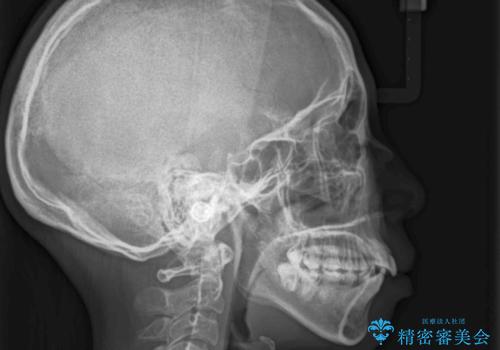

- 前歯のデコボコと上顎の前突感による口の閉じにくさを気にして来院された患者様です。

目立たない装置を希望されたので、上顎が裏側装置のハーフリンガルを選択し、上下左右の小臼歯(計4歯)を抜歯して矯正治療を行うこととしました。

治療期間の目安は2年半~3年間でしたが、咬み合わせにより上顎装置が頻繁に脱落してしまい、治療期間が長期化してしまいました。

期間はかかったものの、口元の張り出し感や歯のデコボコが解消され、患者様には大変満足していただけました。